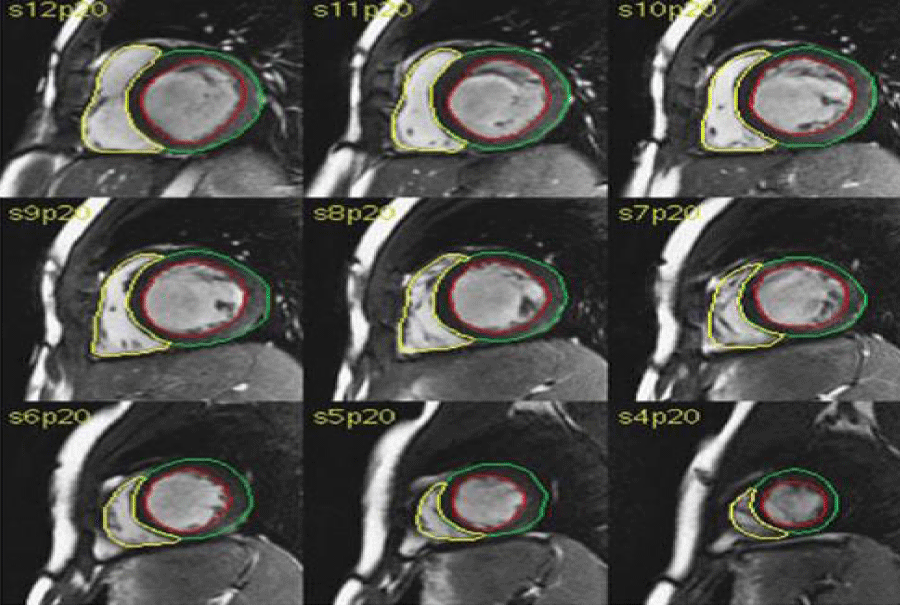

Offline analysis was done with dedicated Philips software. Cine loops were used to choose end-diastole (ED) and end-systole (ES). ED was defined as the phase with the largest RV (and left ventricular (LV)) cavity and ES as the phase with the smallest RV and LV cavity. Tracing of endocardial and epicardial borders was performed manually on each ED and ES short-axis view. The sums of the traced contours in ED and ES were used to calculate ED volume (EDV) and ES volume (ESV) using a disc summation technique. EDV and ESV were used to calculate Stroke Volume (SV) and Ejection Fraction (EF). SV was defined as EDV - ESV, and EF as [(EDV - ESV)/EDV] × 100%, as shown in Figure 2.

Figure 2: RV analysis by CMR.

Analysis of the right ventricle was performed per slice basis by manual contouring of the endocardial and epicardial borders, including trabeculations and papillary muscles as part of the right ventricular volume was calculated based on the Simpson’s method.